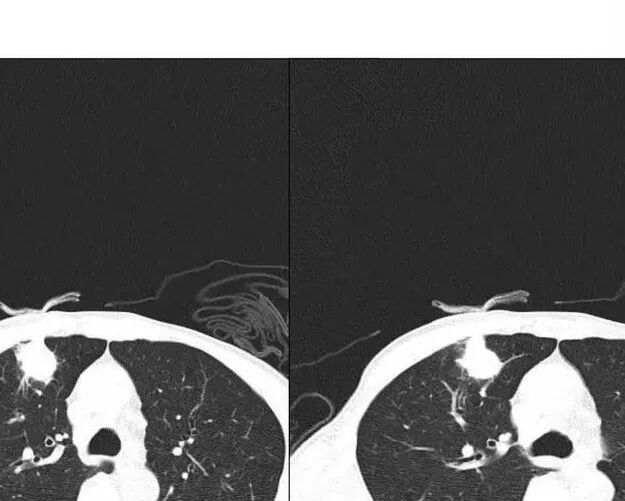

患者男性,70岁;既往有高血压病病史,还有冠心病病史;不嗜烟酒;因头昏入院,查胃镜病理提示鳞状细胞癌,胸部CT提示右上肺占位性病变。

南边:患者男性,70岁;既往有高血压病病史,还有冠心病病史;不嗜烟酒;因头昏入院,查胃镜病理提示鳞状细胞癌,胸部CT提示右上肺占位性病变。

1.胸膜下不规则结节影,密度不甚均匀,有浅分叶、长毛刺,周边有磨玻璃晕。

2.有胸膜牵拉,尽管收缩能力不强。支气管相关(有细小支气管止于病灶内侧),加之病灶孤立、边界不清带晕,这些都不是血道转移病灶的特点。

左锁骨上及纵隔未见肿大淋巴结,注意这是胃癌的淋巴转移路径。

3.病灶没有新旧不等、没有高密度,没有卫星灶,结核的支持点也不多。

综上,更支持慢性炎性病灶。隐球菌感染不能排除,无论是影像特点,还是患者不相关的临床表现。